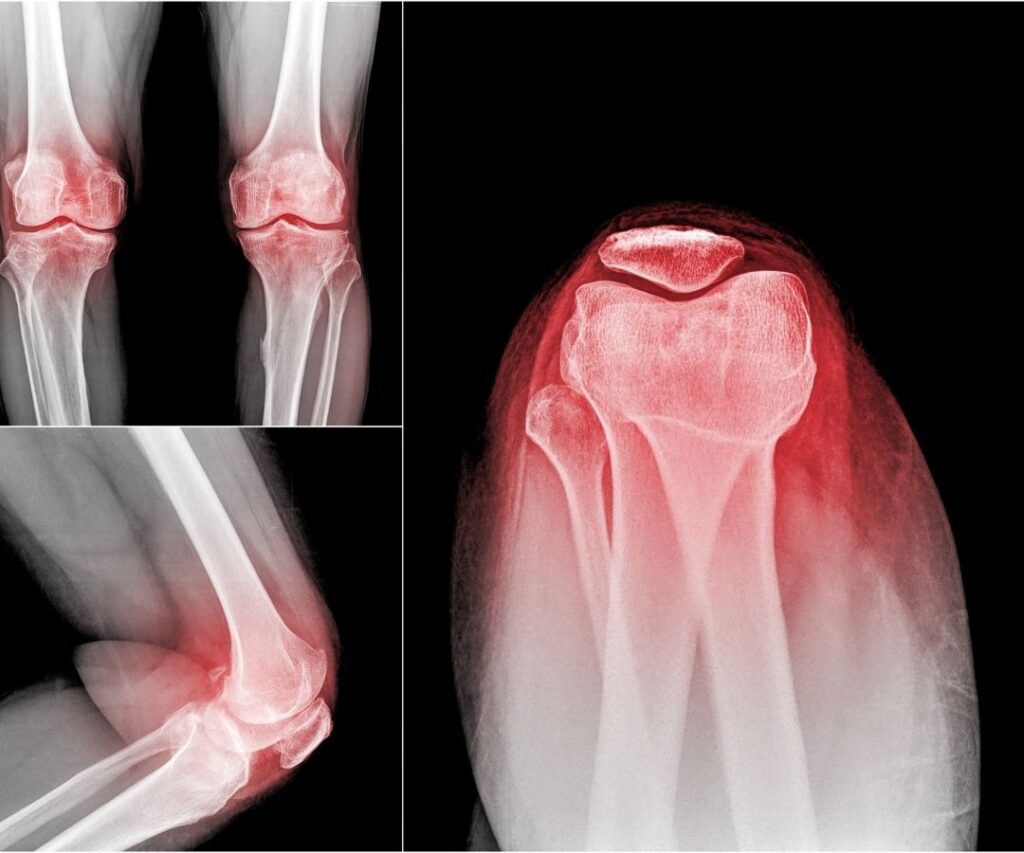

Effective treatment always begins with a precise diagnosis. Our specialists utilize advanced imaging (MRI, X-ray, Ultrasound) and perform thorough physical examinations to pinpoint the exact source of your pain. We take the time to understand your athletic goals and how your injury impacts your life, ensuring the treatment plan is tailored to your unique needs.

We will often order necessary diagnostic imaging, such as X-rays or an MRI, to confirm the diagnosis and review the results with you promptly. Our goal is to provide clarity and a definitive path forward.